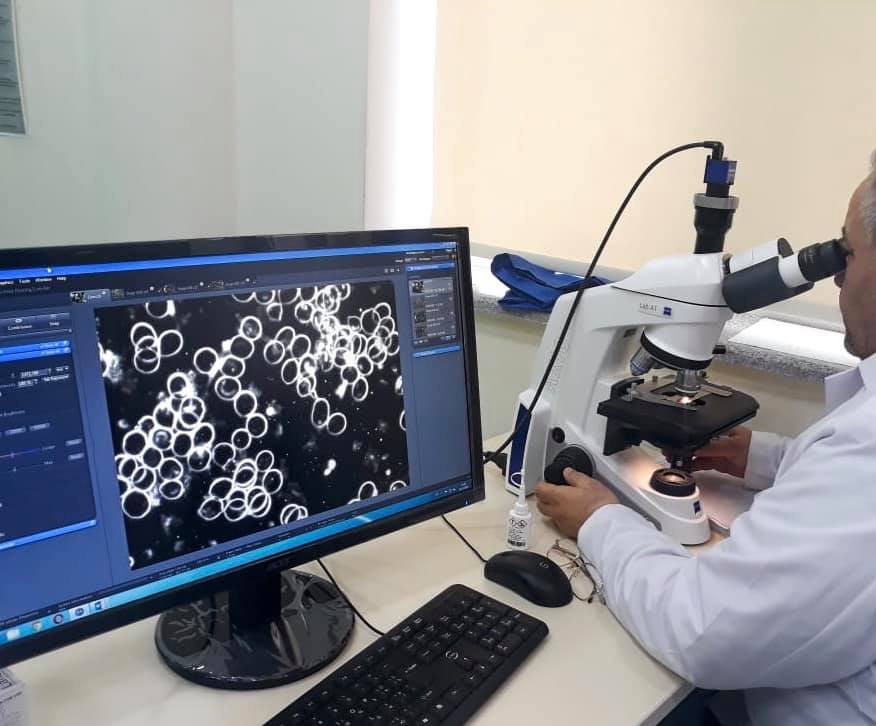

Masallı Bioloji Təbabət klinikasında çoxprofilli cərrahiyyə kabinetləri, 28 çarpayılıq palatalar, tam avtomatlaşdırılmış, müasir avadanlıqlarla təchiz olunmuş laboratoriya, geniş profilli müasir cihazlarla təchiz olunmuş fizioterapiya şöbəsi, MRT (maqnit rezonans tomoqrafiya), KT (komputer tomoqrafiyası), Rəqəmsal rentgen, Panoram rentgen, qastroendoskop, USM və s. diaqnostik cihazlar quraşdırılmışdır. Bundan əlavə, müalicəvi sanatoriya xidməti göstərmək üçün Naftalan palçıq vannaları, Naxçıvan duzundan yaradılmış "aspiratorlu Duz mağarası” bölgə əhalisinin istifadəsinə verilmişdir.